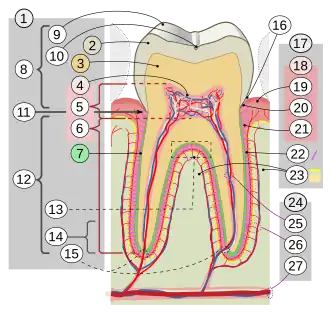

17. Periodontium

:18. Gingiva: ::19. free or interdental ::20. marginal ::21. alveolar :22. Periodontal ligament :23. Alveolar bone 24. Vessels and nerves: :25. dental :26. periodontal :27. alveolar through channel

In dentistry, the crown is the visible part of the tooth above the gingival margin and is an essential component of dental anatomy. Covered by enamel, the crown plays a crucial role in cutting, tearing, and grinding food. Its shape and structure vary depending on the type and function of the tooth (incisors, canines, premolars, or molars), and differ between primary dentition and permanent dentition. The crown also contributes to facial aesthetics, speech, and oral health.

The anatomical crown refers to the portion of a tooth covered by enamel, it includes three main layers: enamel, dentine, and the pulp chamber.[3]

The pulp chamber is the innermost part of the anatomical crown and contains blood vessels, nerves, lymphatics, and odontoblasts.[3] It plays a role in dentine formation, nutrient delivery, and pain response.

Though mainly associated with root canal treatments, the pulp chamber's position within the crown is important in clinical practice. Several anatomical "laws" have been described to aid in locating the pulp chamber during restorative or endodontic procedures:

- Law of centrality: The pulp chamber is always located in the centre of the tooth at the level of the cementoenamel junction (CEJ).[10]

- Law of concentricity: At the CEJ level, the pulp chamber walls are concentric to the external surface of the crown.[10]

- Law of the CEJ: The CEJ is the most consistent landmark for locating the pulp chamber.[10]